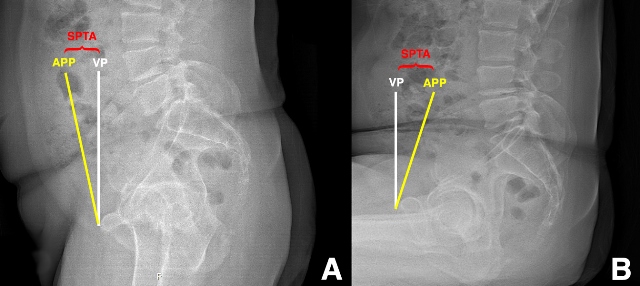

Ranawat et al. [9] explored the effects of fixed versus flexible spinopelvic relationships on the functional position of the acetabular component in a cohort of primary THA patients using frontal and lateral radiographs acquired in standing and sitting positions (Figure 1A-B). Compared to those patients with relatively flexible spinopelvic relationships, they defined those with more rigid spinopelvic motion as having less than 10 degrees of change in sagittal pelvic tilt from standing to sitting position. Of the 68 patients included for the study, over 70% had evidence of spinal pathology and 25% met the authors’ definition of having a stiff spine, or “fixed pelvis”. Flexible patients exhibited slight anterior sagittal pelvic tilt in standing to more substantial posterior tilt in sitting, the effect of which increased functional anteversion of the acetabular component by 0.75 degrees per degree of posterior tilt as they sat. Presumably, increased functional anteversion is protective against posterior dislocation during sitting. For patients with fixed spines, there was significantly less functional acetabular anteversion in the sitting position (i.e. less protection against posterior THA instability). The authors conclude that a dynamic assessment of spinopelvic motion should be part of the preoperative planning for THA. For THA patients with flexible spines, they recommend reproducing native acetabular anteversion, and they speculate that patients with flexible spines do not necessarily require pelvic tilt-adjusted anteversion, as prior publications have suggested [5]. However, they recommend increasing acetabular component anteversion in patients without normal posterior pelvic tilt in sitting.

Figure 1: Preoperative sagittal pelvic tilt angle (SPTA) measurements standing (A) and sitting (B) lateral pelvic radiographs. SPTA, sagittal pelvic tilt angle between the anterior pelvic plane (APP, yellow line connecting the antero-superior iliac spines to the pubis) and the vertical plane (VP, white line). There is anterior sagittal pelvic tilt relative to the VP in standing, and there is posterior sagittal pelvic tilt in sitting.